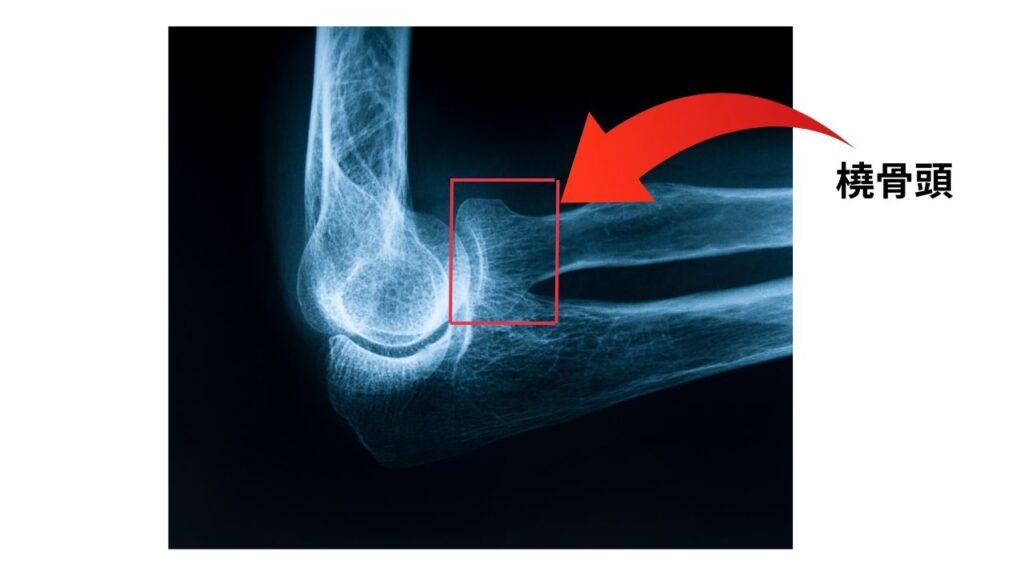

肘内障は、正式には「橈骨頭亜脱臼(とうこつとうあだっきゅう)」と呼ばれます。「橈骨(とうこつ)」という前腕の骨の先端部分が、肘関節を包む靭帯から部分的に外れてしまう状態です。一般的には「肘が抜けた」と表現されることが多いですが、骨が完全に外れる脱臼とは少し違います。

- 骨格の特徴: 橈骨の先端がまだ小さく、靭帯が骨をしっかりと固定できていません。

そのため、少しの力が加わるだけで、大人では起こらないような亜脱臼が起きてしまうのです。骨折とは異なり、レントゲンには写らないことがほとんどです。